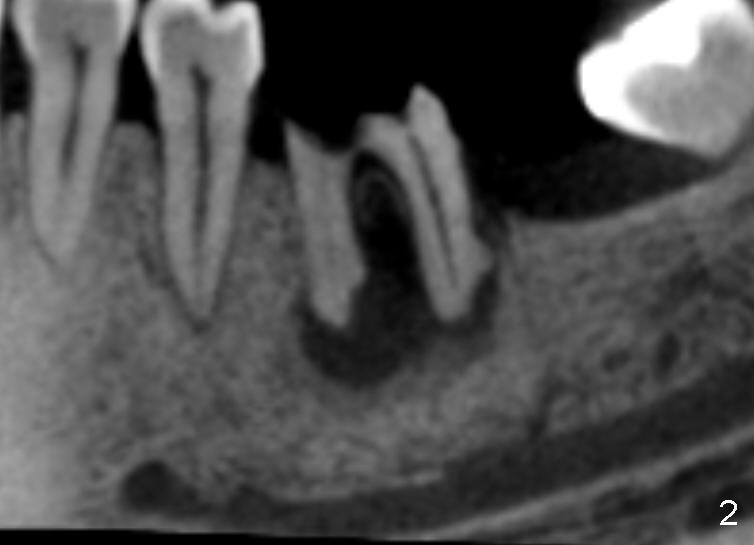

A 46-year-old female patient requests restoration of the lower left 1st molar (Fig.1). Although the patient refuses diabetes treatment, her wounds usually heal uneventfully. Her gag reflex is active. She could not tolerate a removable partial denture, which replaced the missing 2nd molar. Preop PA and CT shows extensive bone loss around the residual roots (Fig.1,2,4). It appears that extraction is simple. Immediate implant should not add too much additional trauma (Fig.3,5). Arrowheads in Fig.3,5 indicate the extent of osteotomy for implantation. With meticulous surgical manipulation, the wound should heal normally.